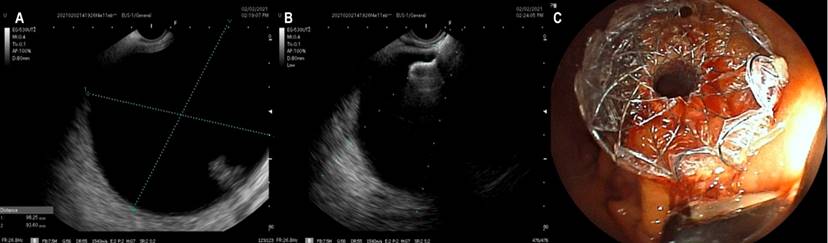

Los pacientes se realizaron con sedación asistida por anestesiología, en la que se empleó propofol, no se requirió anestesia general en ningún caso. Como profilaxis antibiótica se usó ciprofloxacina 400 mg IV (dosis única). Se usó un ecoendoscopio lineal Fujifilm EG-530UT2 con procesador de ultrasonido SONART SU-1 operado por un ecoendoscopista experto. Una vez evaluada la colección mediante USE (Figura 1A), se realizó una punción mediante una guía Doppler para comprobar la existencia de vasos interpuestos.

Todos los drenajes se realizaron al estómago. En solo 4 casos se utilizó aguja de punción 19 G y paso de guía de 0,035 bajo visión ecoendoscópica para tener mayor seguridad de no perder el trayecto; sin embargo, en los siguientes casos no se usó aguja ni guía, teniendo en cuenta una mejor familiarización con el nuevo stent y su facilidad de uso, además de una buena ventana ecográfica (Figura 1B) y tamaño mayor de 6 cm de diámetro de los pseudoquistes. En todos los casos se utilizó una unidad electroquirúrgica ERBE VIO 200 s en modo de corte puro a 200 W efecto 6. No realizamos cultivo de las muestras obtenidas. En ningún caso se documentó absceso o áreas de necrosis amurallada. Es muy importante tener en cuenta que no se usó fluoroscopia, por lo que no hubo necesidad adicional de emplear medios de contraste.

En ninguno de los casos usamos balones de dilatación. La expansión radial de estos dispositivos es adecuada y consideramos que no es necesaria para mejorar los desenlaces (Figura 1C). El diámetro más empleado fue de 15 mm (11 pacientes) y 10 mm en (2 pacientes). La decisión de usar estos calibres fue por la disponibilidad en las instituciones de estos diámetros en el momento respectivo.